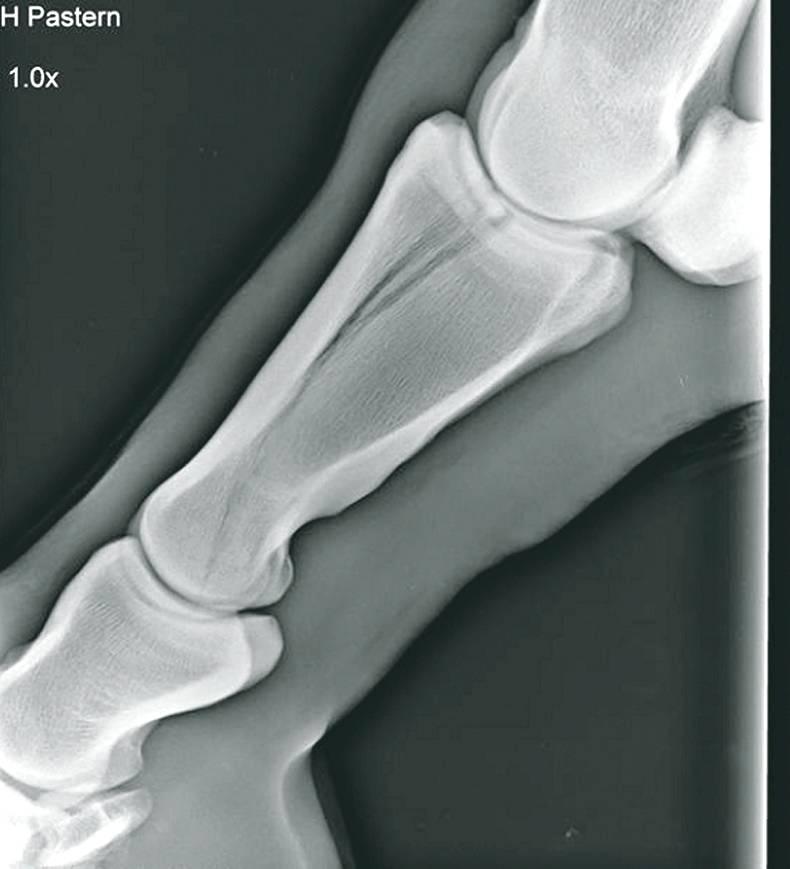

THE stifle joint is a large hinge joint found in the horse’s upper limb and is the equivalent to the human knee. It is formed with the articulation of the lower part of the femur, the upper tibia and the patella.

Although we loosely refer to the stifle as one joint, it is actually split into three smaller joints – the medial femero-tibial joint, the lateral femero-tibial joint and the femero-patella joint. Recognising these individual joints is important when localising specific lesions which affect the specific joints.